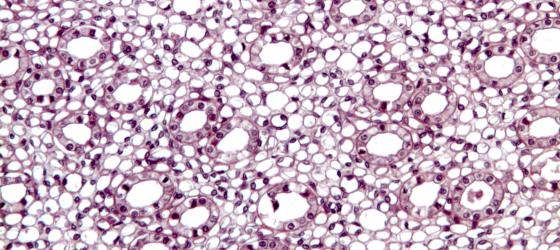

Sudan III e Sudan Black

Queste colorazioni servono per evidenziare elettivamente le goccioline lipidiche contenute nelle cellule adipose. Le sezioni si ottengono da pezzi congelati e tagliati al criostato in modo da evitare i successivi passaggi nei solventi organici necessari per l’inclusione in paraffina che scioglierebbero irrimediabilmente le goccioline lipidiche. Il Sudan III colora le goccioline lipidiche in giallo-arancio mentre il Sudan Black le colora in nero. Qualora si debba fissare il tessuto è preferibile usare una miscela a base di sublimato corrosivo o il formolo-calcio perchè, fissando in tempi molto brevi, si previene lo scioglimento dei lipidi.

Figura S17. Mesentere di topo. Sezione ottenuta al criostato a -40°C per evitare i passaggi in solventi organici che avrebbero estratto i lipidi presenti. Questa colorazione elettiva evidenzia con un precipitato nero la gocciolina lipidica contenuta nella cellula adiposa. Sudan Black 63x

Figura S18. Mesentere di topo. Colorazione elettiva per il tessuto adiposo su sezioni ottenute al criostato. Sudan III 63x